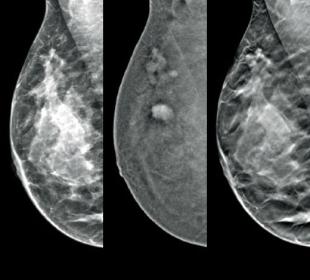

Screening en diagnose